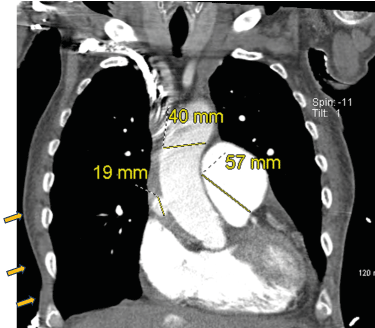

His initial admission workup included a CTA chest to rule out PE, but it showed a penetrating ulcer with a 19 mm saccular pseudoaneurysm of the ascending aorta with intramural hematoma (Figure 1), ectatic thoracic aorta, and pulmonary artery aneurysm measuring 5.7 cm. Cardiothoracic surgery evaluated the patient in the ER, and determined he was not a surgical candidate due to end-stage respiratory failure with other comorbidities. Also, the patient did not prefer the surgical option.

Figure 1.  Day 1 Coronal CT of the Chest

Coronary angiogram with right anterior oblique view of right coronary artery showing spontaneous coronary artery dissection. Main pulmonary trunk is enlarged, measuring up to 57 mm. Ascending aorta is 40 mm. There is a 19 mm outpouching of contrast from the ascending aorta.